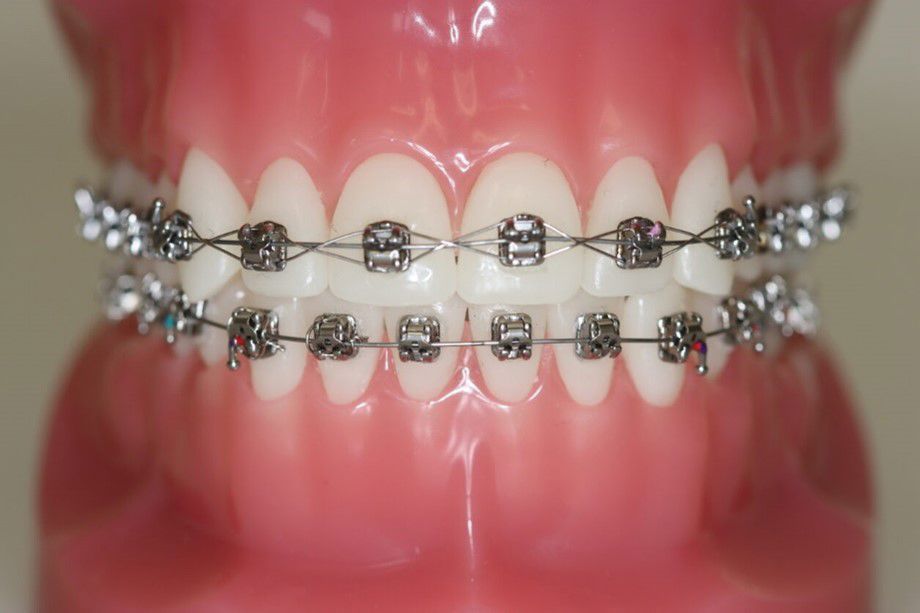

Fastsiddende bøjler

Brackets eller ”togskinner” bliver limet fast på tænderne. Oftest er det nødvendigt med fastsiddende bøjler i både overkæben og underkæben.

Tilvænning

Det kan tage op til en uge, at vænne sig til brackets.

I starten kan opstå en lille blæne eller et lille sår i slimhinden. Du får voks med hjem til at sætte på brackets.